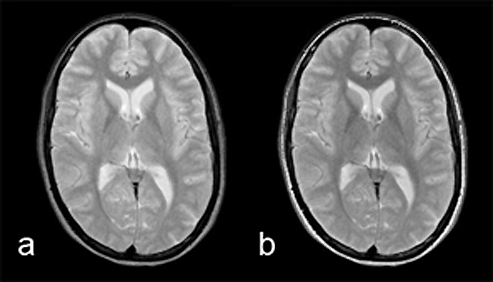

Figura 10-07:

Comparison of rapid spin echo and con­ven­ti­o­nal spin echo. Left: RSE: ETL = 8; eff. TE = 64 ms; ES = 16 ms; TR = 3000 ms

Right: SE: TE = 64, TR = 3000 ms.

With the exception of the signal from sub­cu­ta­neous fat, contrast is very similar.

In RSE images, the lipid signal is usually higher than on si­mi­lar SE images. This is claimed to be caused by several factors, including spin coup­ling among glyceride pro­tons.

There are also magnetization-transfer phenomena that cause protein con­tai­ning tis­sues to appear darker than on similar SE images, whereas hemorrhage with he­mo­si­de­rin will appear less dark and CSF will appear relatively brighter, obliterating con­trast between the ventricles and, e.g., periventricular multiple sclerosis pla­ques.